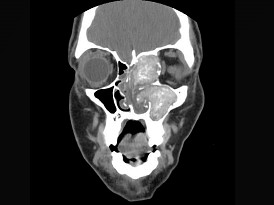

15.17岁男性,左侧上睑下垂,CT检查如图所示,请选择正确的描述或诊断 ( )![]() |

| 正确答案:ABCD |